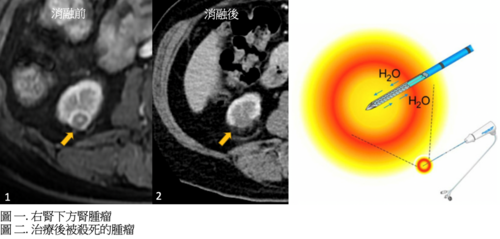

經皮腎腫瘤消融術

如病人身體狀況不適合根治性手術,可以考慮經皮腎腫瘤消融術 去控制腫瘤生長。常用的經皮腎腫瘤消融術包括冷凍消融術和射頻消融術,可用於治療細小(小於4厘米)腎癌腫瘤,醫生會用影像引導將幼針穿刺腫瘤,並透過高溫或低溫將腫瘤殺死。

冷凍消融術

冷凍消融術利用運用氬氦氣體和焦耳湯姆森效應( Joule Thompson Effect)於腫瘤內產生結冰及溶冰效果,將腫瘤細胞殺死。

射頻消融術

射頻消融術中使用的幼針會釋放出射頻能量,並在治療區內產生熱能,將其溫度提升至攝氏60度以上以達到殺死腫瘤細胞的效果。